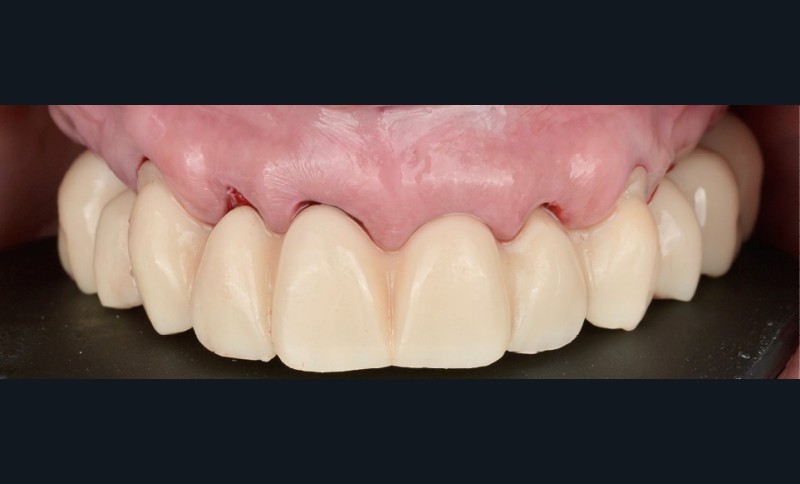

Elle est réalisée en zircone monolithique usinée puis stratifiée manuellement (fig. 9). Dans cette approche hybride numérique-analogique, la CFAO assure la précision de la structure, tandis que la stratification manuelle apporte la personnalisation esthétique et la vitalité du rendu [4]. Le résultat illustre la convergence entre précision technologique et sensibilité clinique (fig. 10).